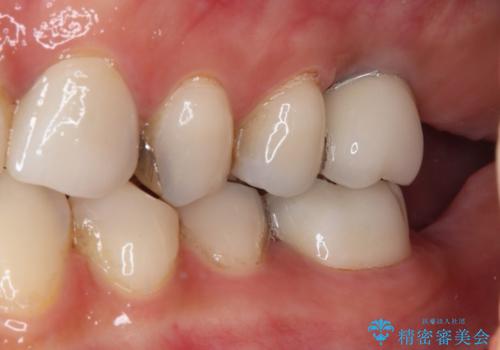

神経が除去されている歯、根管治療の必要な歯、むし歯の非常に大きな歯に対してオールセラミッククラウンにて補綴治療を行うこととしました。

左上の欠損部はインプラントを埋入した上で補綴することとしました。